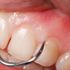

Diş eti kabusundan kurtulabilirsiniz